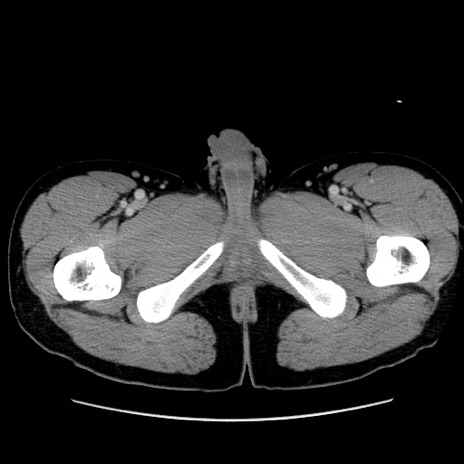

症例36(横断像)

【症例】20歳代 男性

【主訴】心窩部痛

【現病歴】今朝より上腹部痛あり。一旦軽快していたが再度出現したため救急要請。昨日夕に白身の魚を含む刺身を食べた。

【身体所見】BP 136/89mmHg、HR 74/min、BT 37.0℃、腹部:膨満、軟、心窩部に圧痛あり。反跳痛なし、筋性防御なし、腸雑音やや亢進あり。

【データ】WBC 17700、CRP 0.48